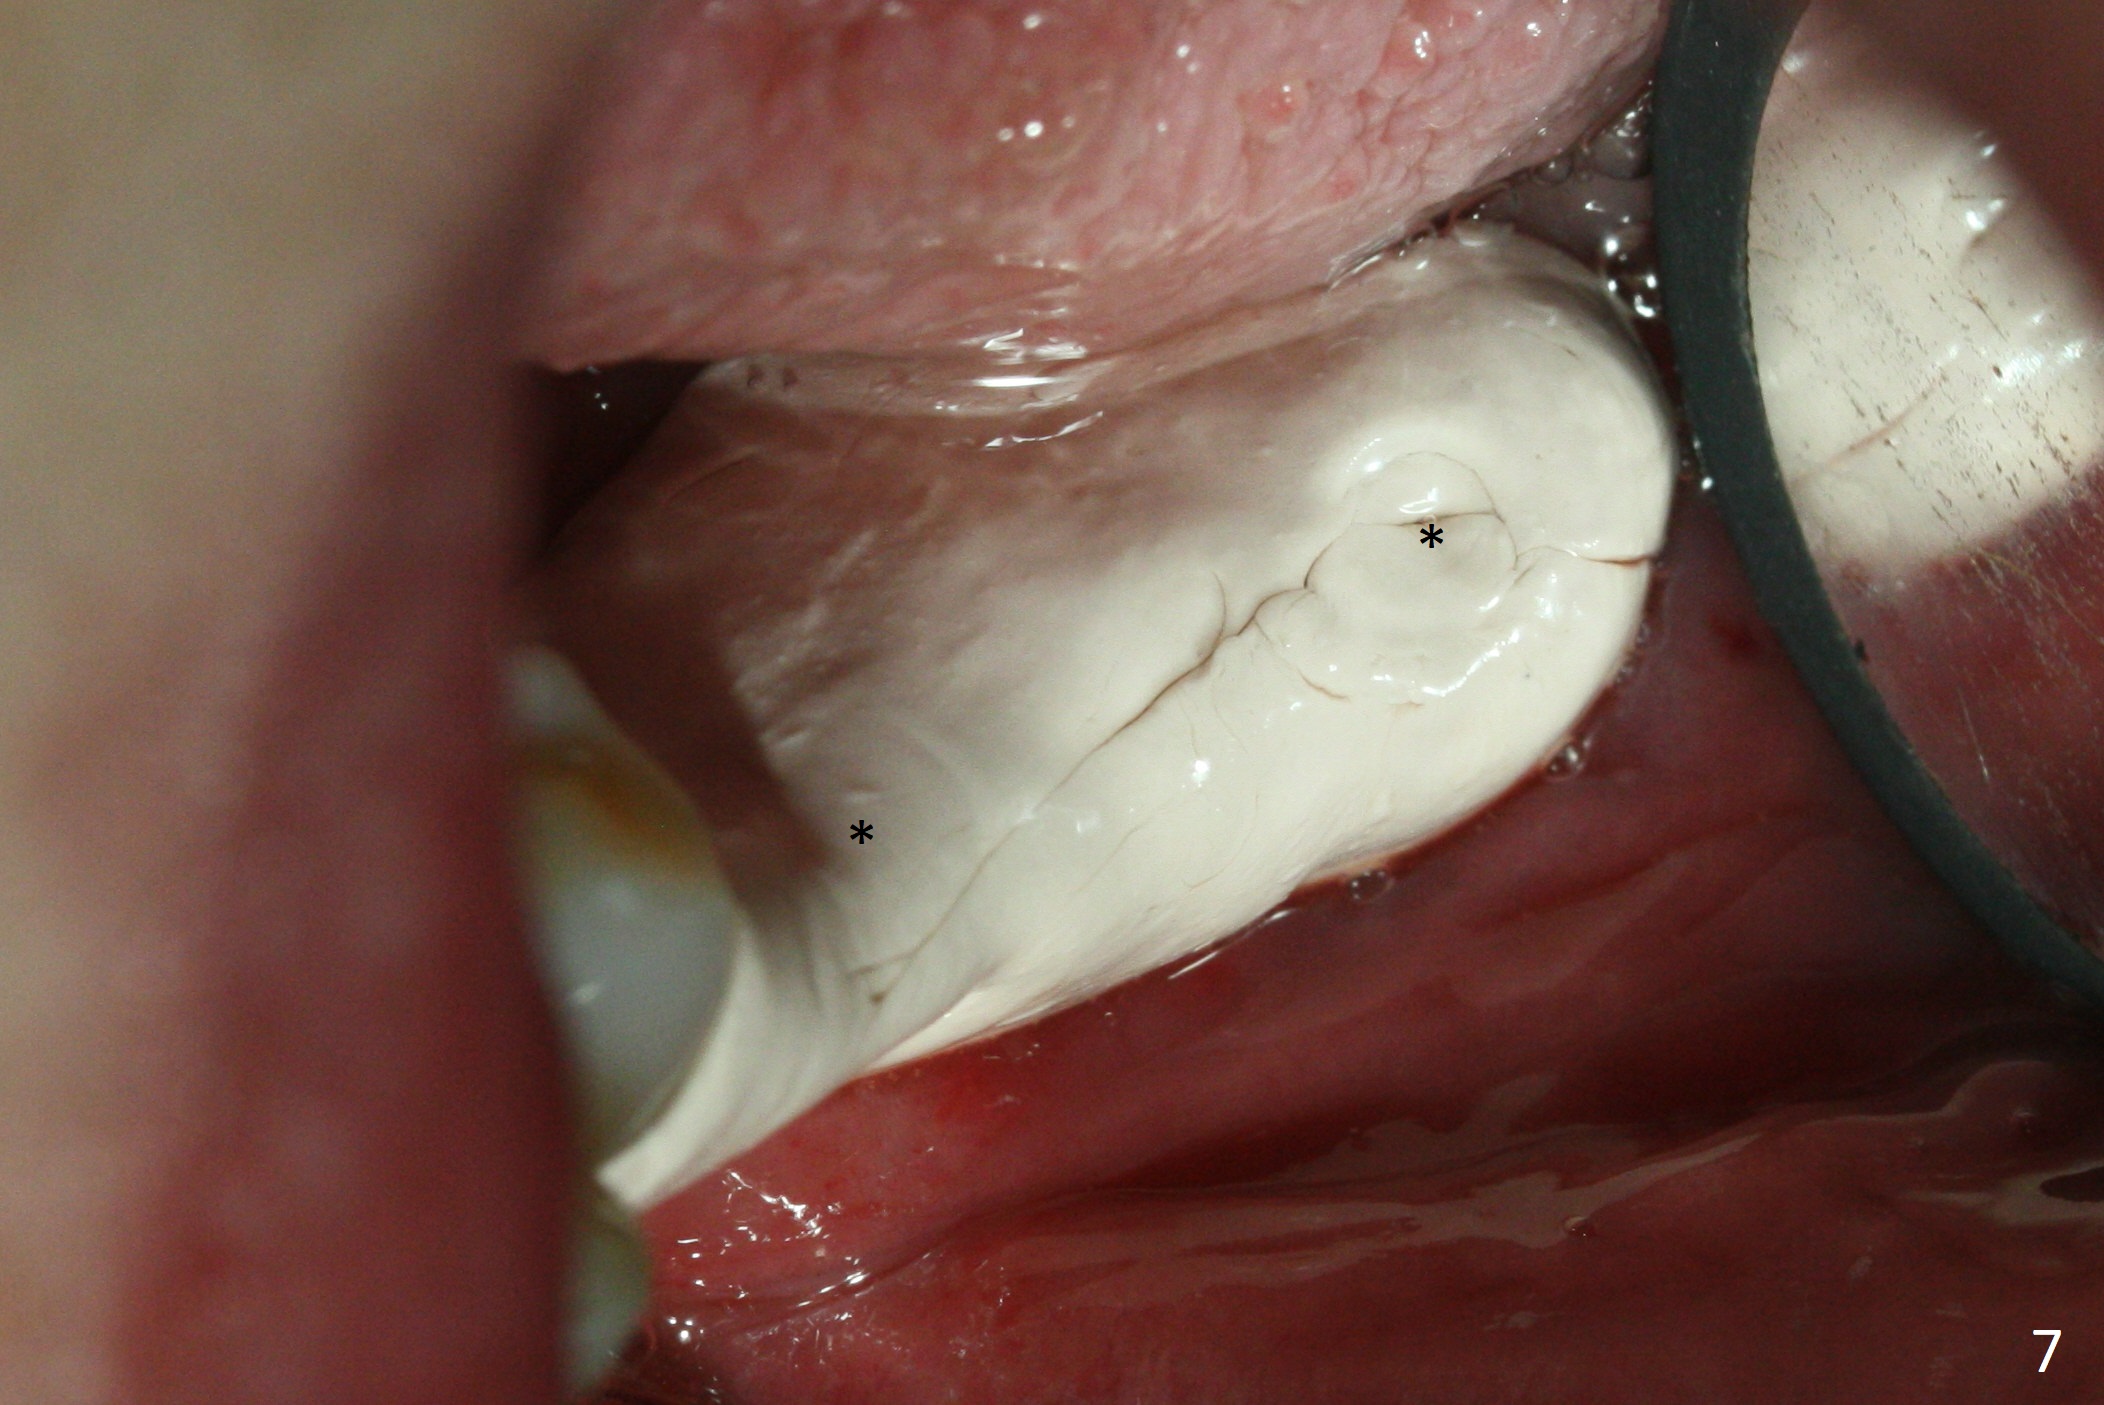

Preop photo shows severe mesial tilt of the tooth #18 (Fig.1). After extraction, the osteotomy is established in the apical end of the socket, where the buccolingual width is limited. It appears that an extra wide implant (5.9 mm) may perforate one of buccolingual plates. On the other hand, the buccal plate (Fig.2 double arrows) is intact and approximately 2 mm tall, whereas the lingual one is thin and lower. Initial osteotomy confirms that bone heights at #18 and 19 are 6 and 8 mm, respectively. Counting 2 mm of the buccal plate and bone graft lingually, a 8 mm long implant may be a practical option at the site of #18. After initial placement of two of 5x8 mm SM implants (Fig.3), the depth of the implant at #19 is adjusted twice (Fig.4,5). With placement of autogenous and allograft (Vanilla, Fig.5 *)) and abutments, a piece of cotton pellet is placed in each abutment well (access, Fig.6 *). Periodontal dressing is applied to the abutment wells for additional retention (Fig.7 *). Due to local poor oral hygiene, splinted provisional is fabricated 4 months postop (Fig.8) in preparation for limited orthodontic uprighting the tooth #20. The patient has pain with mastication at #18 eleven months post cementation (Fig.9). It appears that both of the implants should be removed with immediate replacement and bone graft. Prepare 4 PRF and sticky bone. The new implant will be 5.0 or 5.5x5 mm (Fig.10 green) with 2.3 mm platform (white). A block graft will be harvested from the ipsilateral ramus using 9/8 and 6/5 mm trephine burs for 2-3 mm in depth (Fig.11 blue). The ring graft will be seated around the platform over the implant (Fig.12).